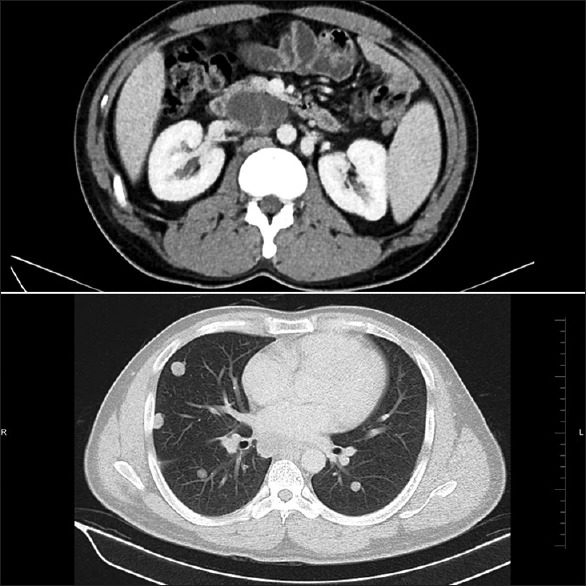

A 29-year-old male patient, with no prior known medical or dermatological comorbidities or any drug allergy, was diagnosed as a case of Stage IIIB testicular cancer. Contrast-enhanced computed tomography chest, and abdomen was suggestive of the lobulated lesion in paraaortic region with multiple bilateral lung nodules, mediastinal, and hilar lymphadenopathy [Figure 1]. Preoperative tumor marker analysis revealed serum alpha-feto protein level 12,100 ng/ml, serum beta human chorionic gonadotropin (HCG) level 2.39 mIU/ml, and serum lactate dehydrogenase (LDH) level 819 U/L. He underwent right high inguinal orchiectomy in May 2015. Final histopathology report was suggestive of mature cyctic teratoma of right testis with associated features of intratubular germ cell neoplasia [Figure 2]. Postoperative tumor marker analysis revealed serum alpha-feto protein level 126 ng/ml, serum beta-HCG level 2.39 mIU/ml and serum LDH level 292 U/L. Patients pulmonary and renal function tests were normal. He was started on bleomycin (30 units on days 1, 8, and15), etoposide (100 mg/m2 on day 1–5), and cisplatin (20 mg/m2 on day 1–5) based chemotherapy (BEP chemotherapy) as per our institutional protocol. However, after 3 cycles of chemotherapy, the patient started complaining of pruritic linear rashes which patient noticed first over the trunk and then gradually increased to involved skin over the chest, back, shoulder, and bilateral upper and lower limbs [Figure 3]. On physical examination, linear and streaked pigmentation were seen on bilateral upper limbs, lower limbs, and over chest and back. No other skin lesions were noted. There was no mucosal involvement or systemic upset. A clinical diagnosis of bleomycin-induced flagellate rash and postinflammatory pigmentation was considered. Routine laboratory investigations, including liver and renal function tests, were normal. Bleomycin was withheld from subsequent chemotherapy cycles, and the patient was prescribed betamethasone dipropionate ointment for local application twice a day for 2 weeks. On subsequent follow ups, the itching sensation was reduced was mild hyperpigmentation remained [Figure 4].

| Figure 2:Contrast-enhanced computed tomography abdomen chest showing multiple bilateral lung nodules with mediastinal and hilar lymphadenopathy